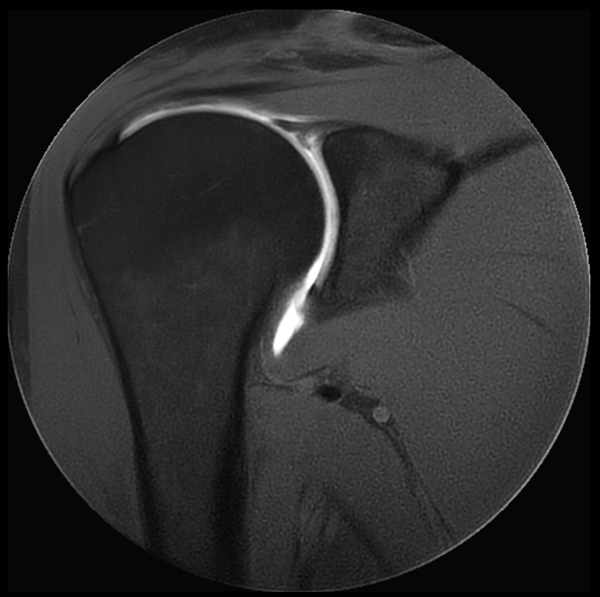

Coronal MultiVane XD - T1w SPAIR